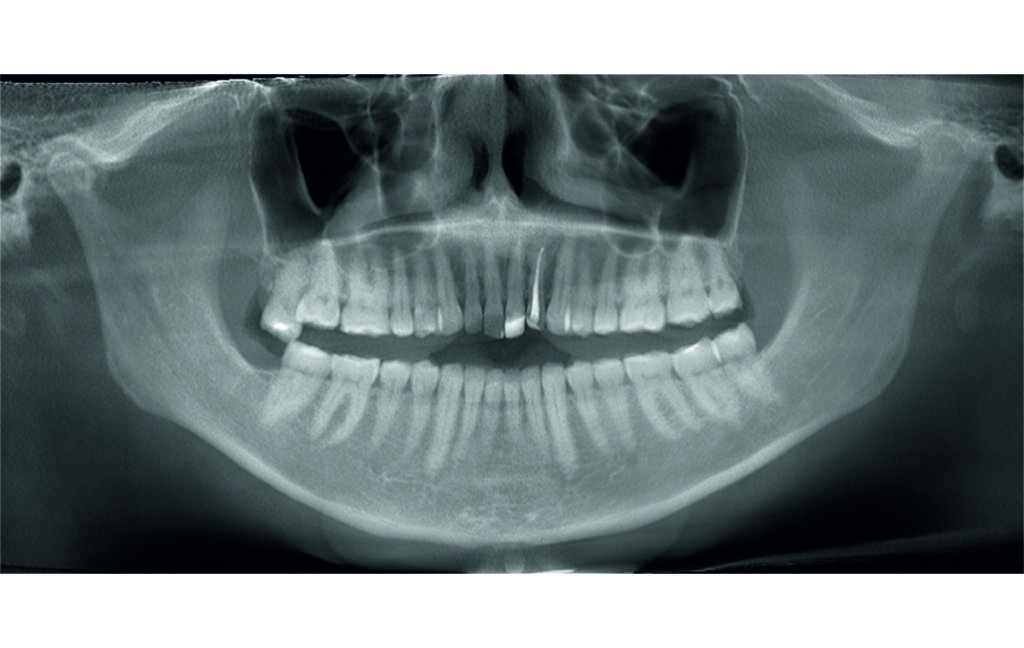

Angle Class II 2mm on the right, Angle Class II 2mm on the left, light mandibular asymmetry to the right, lower central line 1mm to the right, upper central line 1,5mm to the left, 1mm overjet and overbite. Sagittal asymmetry of upper dental arch. Light crowding upper and lower frontal segments, severe attrition of posterior teeth, night bruxism. Normal sagittal position of both jaws, high angle case, steep mandibular ramus,excessive lower facial height, open bite tendency.

The case initially presented as a moderate Class II on the right and a Class II tendency on the left, with tapered dental arches and an anterior open bite extending to tooth 26 in segment II.

In segment I, the open bite reached up to the first premolar.

A 1.5 mm deviation of the upper dental midline to the patient’s left was noted, along with a slight mandibular midline shift to the right, likely due to asymmetrical mandibular growth observed in the facial structure. Severe mesial rotations of teeth 16 and 26 were evident in the initial records. As derotation of 16, 26, 17, and 27 progressed up to aligner 16, the premolars in segments I and II moved distally, resulting in a bilateral Class I relationship, as intended in the initial treatment plan.

Malocclusion Class II on both sides due to mesial rotation of 16 26

Light mandibular asymmetry to the right with both midline deviation.

Severe attrition of posterior teeth, night bruxism. Open bite tendency.